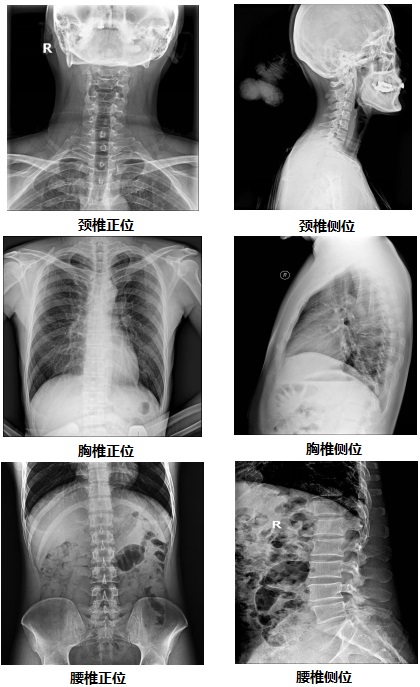

【雙板懸吊式dr機PLD7700D部分臨床效果圖】